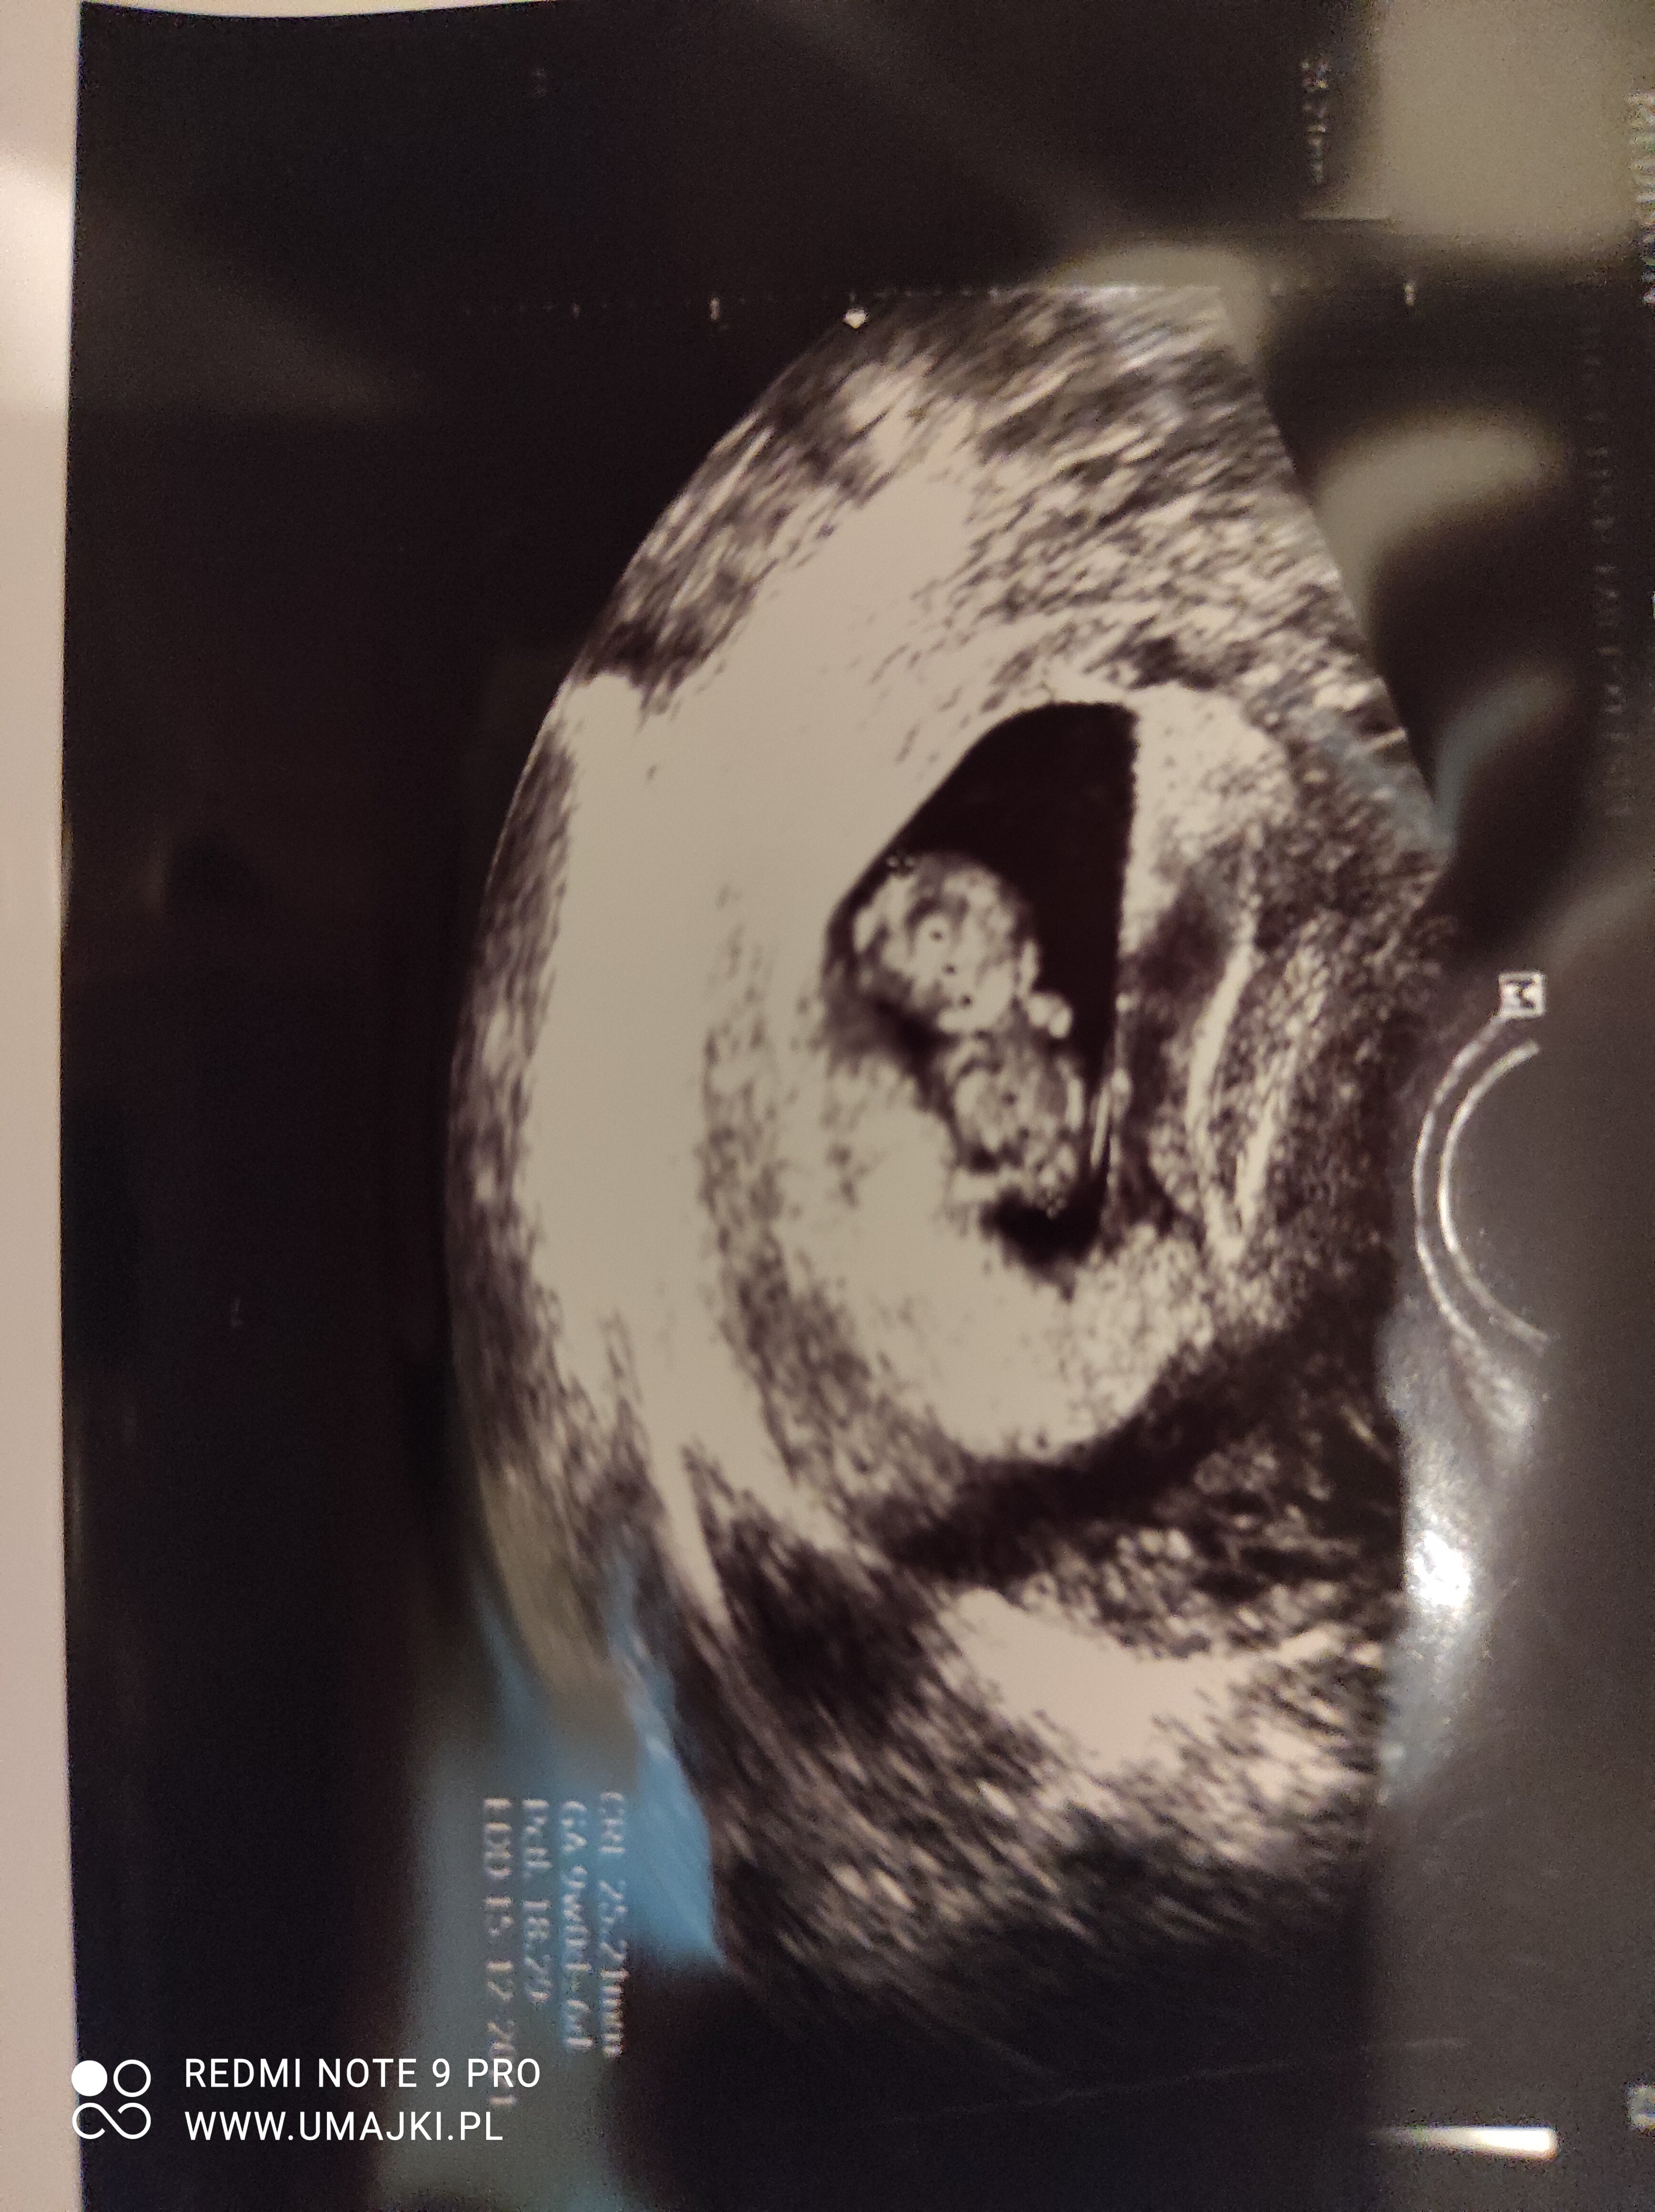

Hej mamusie. Powiedzcie mi czy tutaj jest jedenczy dwa pęcherzyki ? Z pierwszej wizyty w 5 tygodniu i drugie usgz 6 tygodnia. Ginekolog nic nie wspomniał żesą dwa za to przepisał duphaston i luteine. Czy tylko ja tam widzę dwa ?

• 20210512_155147.jpg

20210512_155147.jpg

176,2 KB · Wyświetleń: 150

chyba trochę za duza ta odległość. Może to jakiś krwiaczek ja tez miałam czarna plamę na USG nad pecherzykiem właściwym właśnie w 5t to lekarz mówił że nie wie co to może będę z tego krwawić. Ale minęło i na razie cisza.

nie znam się ale może to krwiaczek ? Z tego co pamietam na moim usg wyglądał podobnie do pęcherzyka 🙈 przynajmniej dla mnie 😉

Myśle ze lekarz powiedziałby Ci o drugim pęcherzyku, to dość istotne 😉